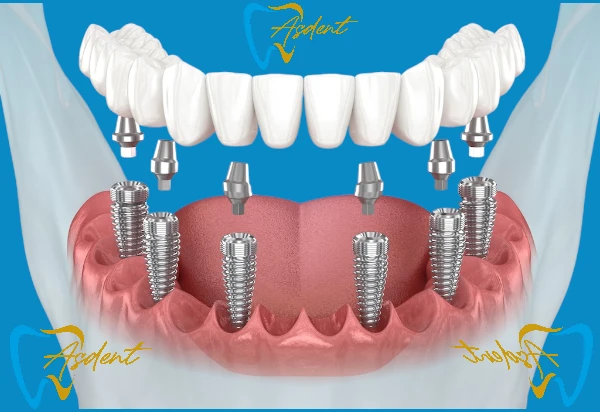

Пакет имплантатов All-on-6 / Имплантация в Турции

- 6 имплантатами с полными зубами на челюсти

- Более прочные и долговечные результаты

- Необходимые рентген, томография и консультация

- Регулярные контрольные приемы после лечения

Преимущества: Дополнительная прочность и долгосрочный комфорт благодаря большему количеству имплантатов.

Пакет имплантатов All-on-8 / Имплантация в Турции

- Полный зубной ряд, поддерживаемый 8 имплантатами, фиксированный протез.

- Максимальная прочность и долговечные результаты.

- Включает панорамную рентгенографию, 3D CBCT-сканирование и подробную консультацию.

- Регулярные контрольные приемы после лечения.

Преимущества: Равномерное распределение силы на челюстной кости благодаря 8 имплантатам, дополнительная прочность, комфорт и долгосрочный успех, эстетический и функциональный результат, максимально приближенный к естественным зубам.